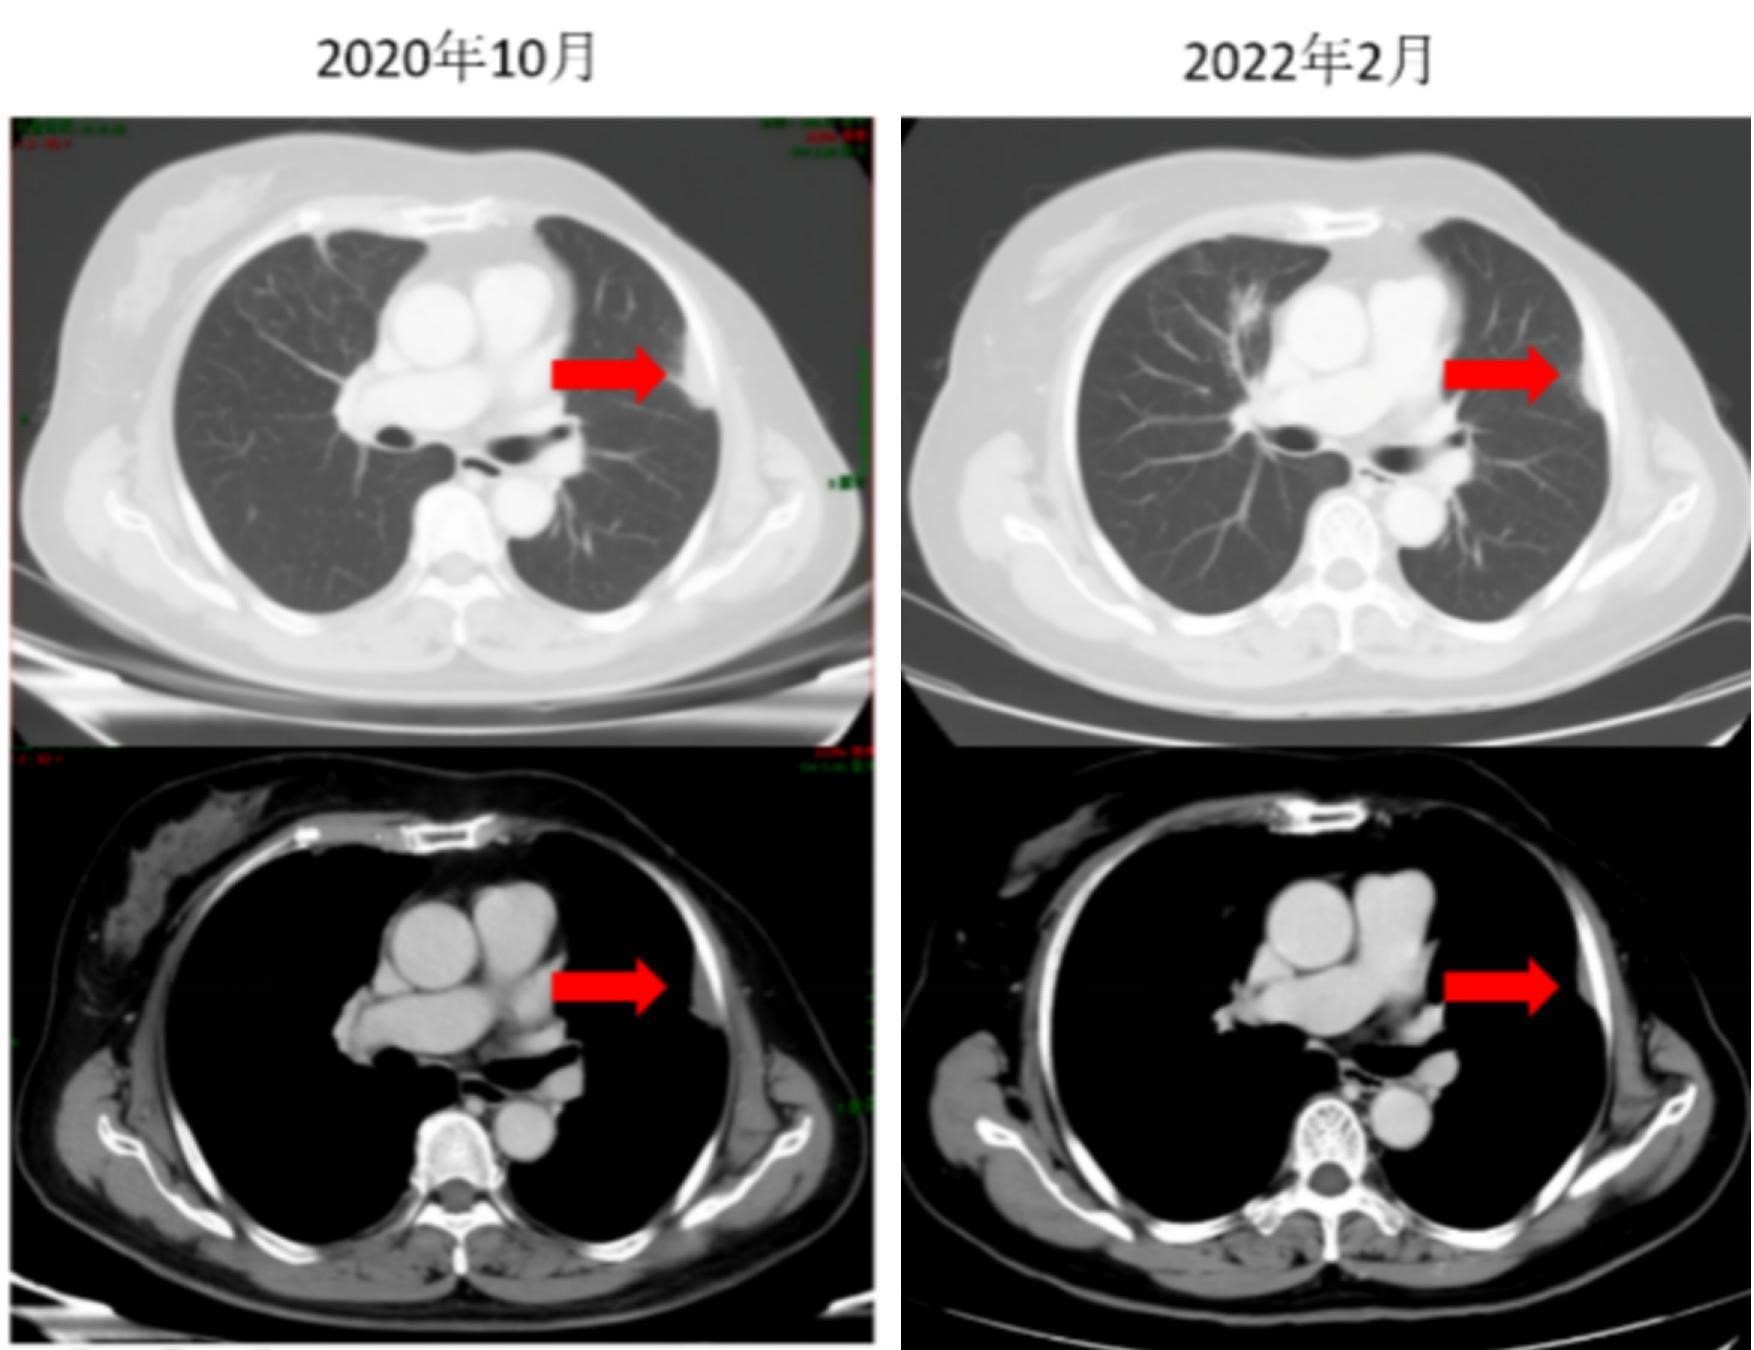

治疗:自2019年11月29日始,进行氟维司群 500mg 皮下注射 第1天 + 长春瑞滨软胶囊 100mg口服  第1,8,15天(每28天一周期,每2-3周期复查,至今共行32周期治疗),唑来膦酸 4mg 静脉滴注,每28天1次。

疗效评估:症状体征变化:胸痛及咳嗽逐渐缓解;辅助检查改变:肿瘤标志物逐渐下降(图2,图3);影像学评估:肿瘤较前缩小,评价PR(图4,图5);不良反应:I度恶心及I度呕吐。

图6 CT示胸膜转移灶缩小

图7 CT示胸膜转移灶进一步缩小

随访:患者于2019年11月就诊后行口服长春瑞滨软胶囊+氟维司群联合治疗,至今已行32周期,现CT等检查示疾病控制良好,仍继续当前方案维持治疗和随访中。

对于该患者疾病稳定后的维持治疗选择,目前并无更多的数据,需综合考虑患者的耐受性及不良反应。目前肺部及淋巴结病灶较前显著好转,转移瘤明显缩小,疗效评价达到PR,耐受性好,长期维持治疗,疾病控制稳定,已经进行32周期,获益时间长,继续当前方案维持。如果疾病控制良好,但是不良反应难以耐受,可将口服长春瑞滨进行减量,或者口服长春瑞滨节拍化疗也是一种很好的治疗选择[8]。丹麦和挪威多中心、Ⅱ期、开放标签的NAME研究是首个探寻常规剂量口服长春瑞滨对比长春瑞滨节拍化疗治疗HER2-晚期乳腺癌患者疗效和安全的研究。

本例患者采用了内分泌联合口服化疗的治疗模式,PFS达30个月,延缓了HR+HER2-耐药的发生,有效延缓了HR+、HER2-晚期乳腺癌患者疾病进展。为长春瑞滨与内分泌治疗联合应用提供了证据。尤其该患者病理显示具有微乳头状癌成分,这种病理学类型的生物学行为极差,具有极高的复发和转移风险,在这种情况下依然取得如此好的疗效,的确令人欣喜。并且口服长春瑞滨软胶囊较传统的静脉化疗药物的副反应更小,使用方便无需要住院,且可保证患者良好的生活质量。因此,提示内分泌联合口服化疗药物或成为HR+HER2-晚期乳腺癌另一种治疗的选择。